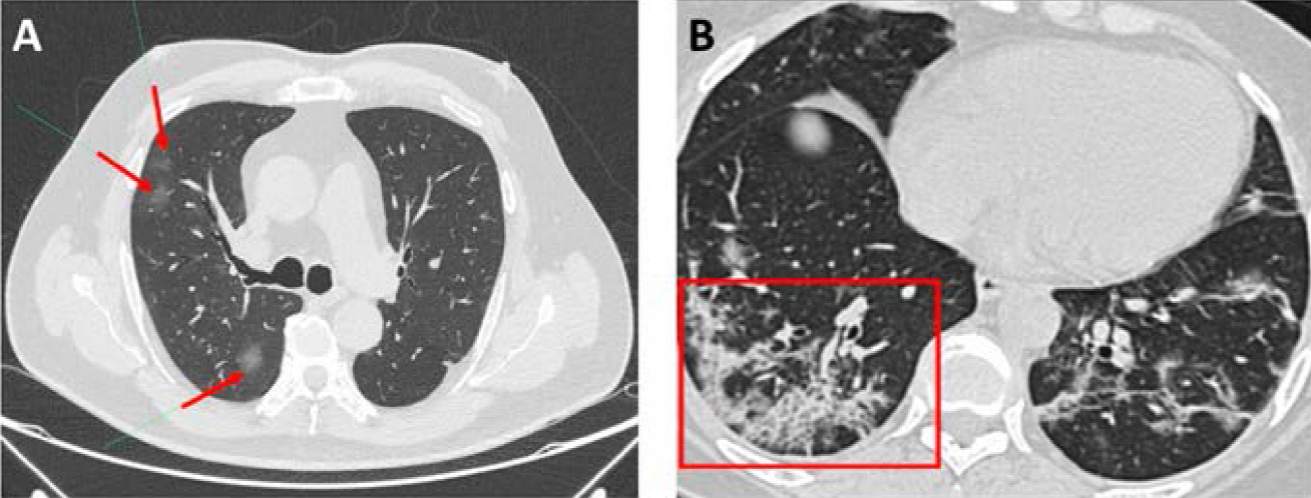

Los hallazgos tomográficos de la COVID-19 son variados y han sido descritos por múltiples series.44,45,46 Aunque dichos hallazgos dependen de la severidad y del estadio de la enfermedad,47 la evidencia sugiere que la principal característica es la presencia de opacidades en vidrio esmerilado (Figura 4A).42 La mayoría de los pacientes presentan un compromiso bilateral, que involucra múltiples lóbulos pulmonares con un marcado predominio de los segmentos inferiores. Otra de las características típicas es que las lesiones siguen una distribución subpleural o periférica.42,43,47 Se ha reportado que las opacidades en vidrio esmerilado pueden asociarse con reticulaciones intralobulares (producto del engrosamiento de los septos intralobulillares), produciendo el patrón en empedrado (crazy paving) (Figura 4B) de 35 a 40 %4 de los casos.44,45 Además, dichas opacidades en vidrio esmerilado pueden confluir y estar acompañadas de áreas de consolidación, produciendo el denominado signo del halo en 64 % de los pacientes.44

Figura 4. Tomografía axial computarizada de alta resolución (TACAR) de dos pacientes con COVID-19. A) Ligeros infiltrados en vidrio esmerilado (flechas rojas). B) Infiltrado en vidrio esmerilado asociado a reticulaciones, que se observa como patrón en empedrado (recuadro rojo).